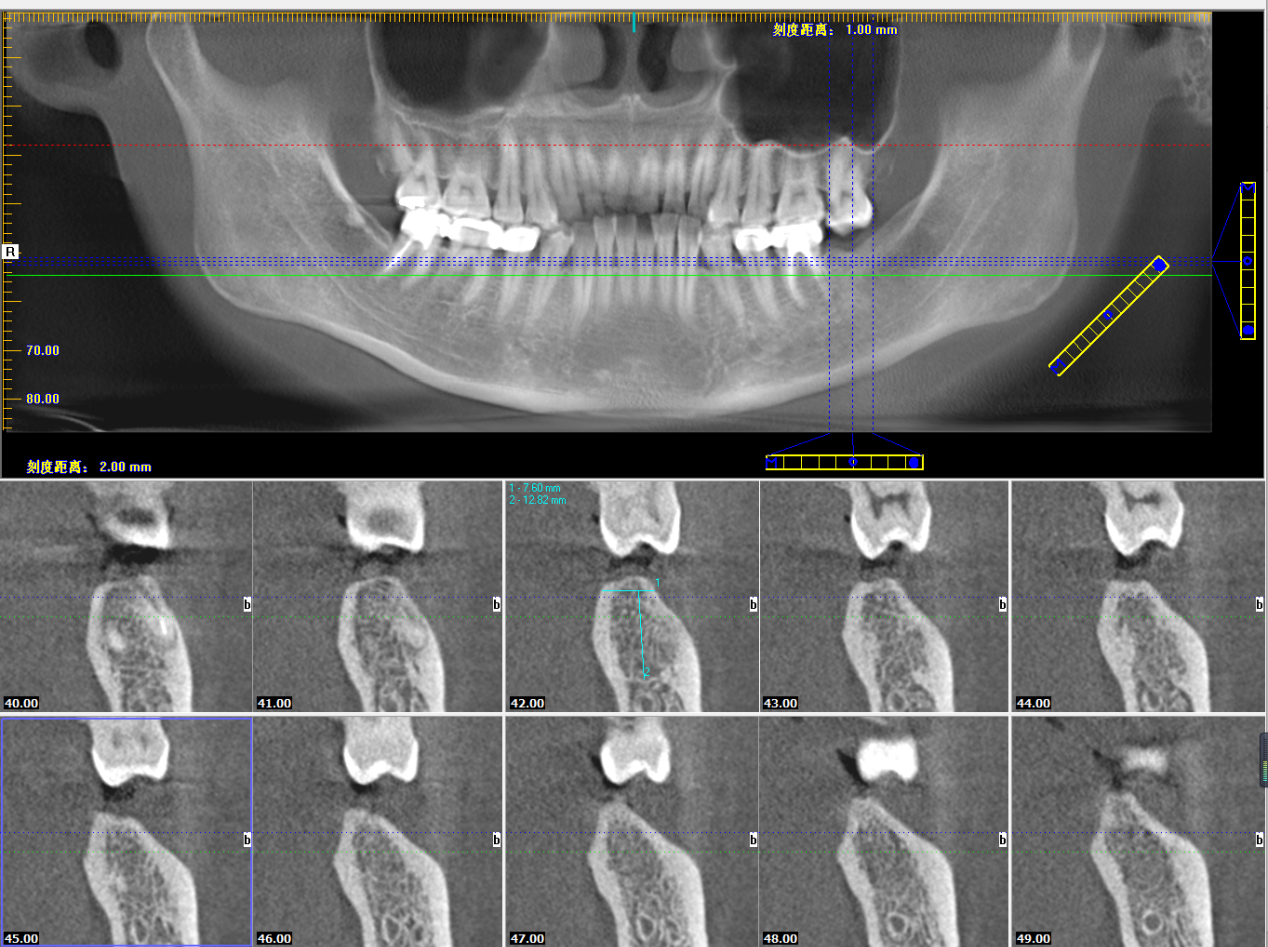

厦门麦芽口腔医院引进的3D数字化导板精准种牙技术,具备极佳的临床效果,“导板精准种”0.01毫米的偏差也不放过,经过了上千例种植病例的临床考验。

其实,对于医生来说,很多时候不能“眼见为实”,肉眼对口腔的观察,远没有CT来得直观、全面、精确,拍摄CT是为了更好的治疗。

本次种植直播患者,韩女士。34岁,左下侧第二磨牙蛀牙缺失,选择韩国OSSTEM种植体。

姚江武院长运用数字化精准种植牙技术,在短短7分钟内,就将种植体植入患者牙槽骨内,展现了高超的种植技术,实现种植过程快速舒适、精准安全、微创无痛的临床效果。